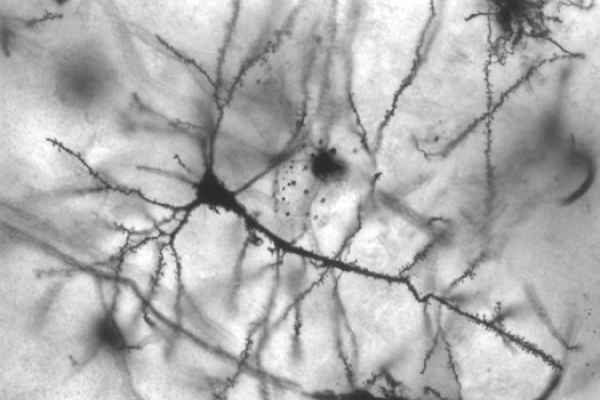

Se sfruttata in tutte le sue potenzialità, l’ultima ricerca italiana in campo neuroscientifico potrebbe rivoluzionare il trattamento di moltissime patologie neurodegenerative, se non tutte. Lo studio condotto dalla dott. ssa Paola Tirassa dell’Istituto di Biologia Cellulare e Neurobiologia del Consiglio Nazionale delle Ricerche (IBCN-CNR), sito a Roma, ha dimostrato che è possibile stimolare la nascita di nuove cellule neurali attraverso l’uso di un particolare collirio, formulato a partire dai progressi già effettuati in questa direzione dalla scienziata Rita Levi Montalcini. Il noto premio Nobel aveva fatto la scoperta negli anni ’50: fu definito per la prima volta il “nerve growth factor“, che sta per “fattore di crescita neurale” ed è una proteina ritenuta responsabile dei processi riparativi e rigenerativi sui neuroni. Gli scienziati che hanno messo a punto la soluzione in gocce oculari sono, dunque, riusciti a dare concretezza alle speranze riposte a suo tempo nella scoperta della Montalcini.

La formulazione del collirio risulta cruciale come mezzo di somministrazione del nfc, in quanto oltre la barriera retinica è presente un accesso diretto ai nervi del chiasma ottico che trasferiscono le informazioni visive alla corteccia visiva primaria, attraversando l’intero cervello umano. Ciò permette alla proteina di agire subito sulle aree danneggiate, in particolare la sua utilità è stata sperimentata nella zona subventricolare laterale. Le cellule progenitrici si troverebbero in questa posizione e reagirebbero in modo immediato al fattore di crescita neurale, che le stimola l’attività ed aziona il loro meccanismo riparativo-rigenerativo. Il nuovo metodo terapeutico è stato pensato per patologie quali encefalopatia diabetica, l’infiammazione cronica o danni da agenti chimici, ma trova utilità pratica anche per fermare il decadimento cerebrale tipico di demenze e malattie come l’Alzheimer ed il morbo di Parkinson.